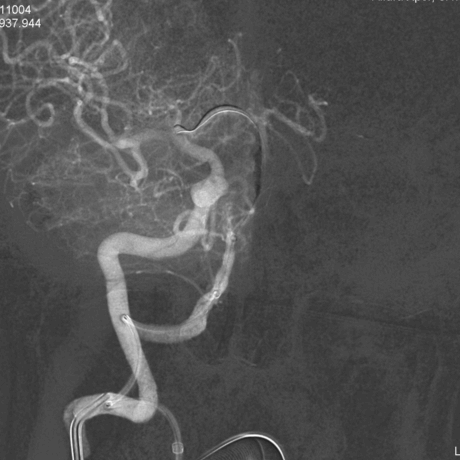

在路图指引下,沿5F中间导管送入微导丝+Echelon-10微导管至右侧椎动脉V4段,多次尝试后微导丝成功通过基底动脉闭塞段,将微导丝头端置于右侧大脑后动脉P2段。

撤除微导管,送入加奇SacSpeed®球囊1.75×12mm,由基底动脉闭塞段远端至近端依次扩张,复查造影发现基底动脉复通。

SacSpeed®球囊扩张后造影。

经5F中间导管送入颅内支架(ENTERPRISE 4.5mm×28mm)至基底动脉狭窄处,准确定位后释放支架。

支架置入后复查右侧椎动脉造影可见基底动脉狭窄明显好转,支架位置形态良好,残余狭窄率30%,前向血流TICI分级3级。